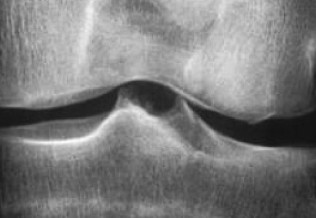

Rhumatologie

Gonalgies